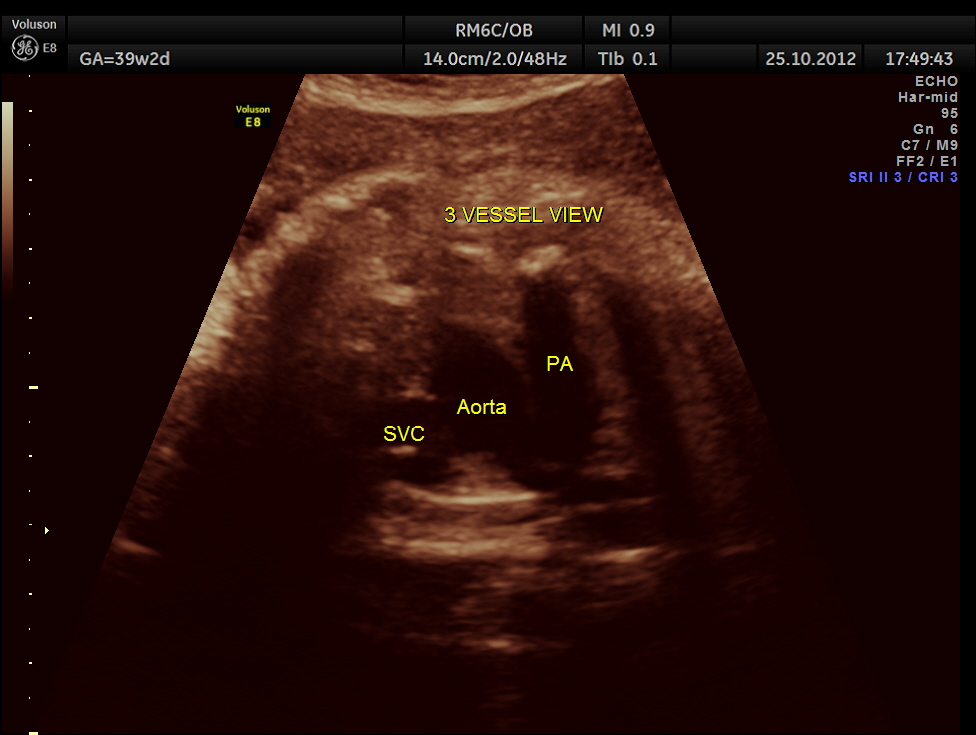

THIS FETUS HAD SEVERE FETAL ANEMIA WITH CARDIAC FAILURE LEADING TO CARDIOMEGALY WITH MITRAL, TRICUSPID AND PULMONARY REGURGITATION .NO OTHER OBVIOUS CARDIAC ANOMALY WAS MADE OUT . THE VENO ATRIAL , ATRIO VENTRICULAR AND VENTRICULO ARTERIAL CONCORDANCE APPEARED TO BE NORMAL; NO SEPTAL DEFECT WAS MADE OUT.